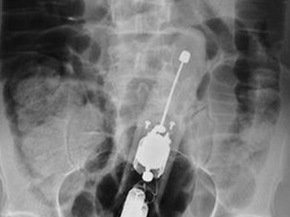

Dương vật giả 23 cm mắc trong bụng người đàn ông

Dương vật giả 23 cm mắc trong bụng người đàn ông Thứ Sáu, 19/10/2012 11:14 (NLĐO) – Theo ...